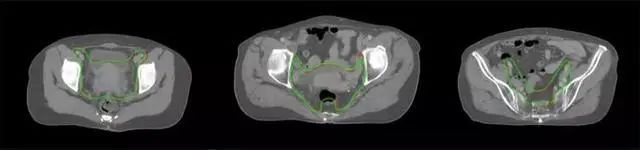

四、放射治療智能勾畫軟件

放射治療,簡稱放療,是治療腫瘤主要手段之一,利用放射線破壞照射區(qū)(靶區(qū))的細(xì)胞,使腫瘤細(xì)胞停止分裂直至死亡,醫(yī)生通常把放射治療形象的比喻為“打靶”,放療前精準(zhǔn)勾畫腫瘤靶區(qū)范圍是腫瘤放射治療的關(guān)鍵步驟。傳統(tǒng)的靶區(qū)勾畫醫(yī)生會(huì)根據(jù)患者多張CT、MRI影像片憑借經(jīng)驗(yàn)進(jìn)行,比較耗時(shí),治療的病人數(shù)量也有限,且靶區(qū)勾畫缺少行業(yè)統(tǒng)一的規(guī)范和標(biāo)準(zhǔn),無法達(dá)到同質(zhì)化,勾畫精確度不理想。

技術(shù)原理

基于深度學(xué)習(xí)人工智能的放療靶區(qū)智能勾畫技術(shù)和自動(dòng)計(jì)劃技術(shù),基于全面的市場調(diào)研和臨床專業(yè)意見,采用獨(dú)創(chuàng)的基于小樣本量的人工智能算法,實(shí)現(xiàn)放療靶區(qū)和危及器官的快速全自動(dòng)勾畫。

產(chǎn)品優(yōu)勢

縮短至幾分鐘內(nèi)便可完成,大幅提升了放療效率,且人工智能平臺(tái)完成的靶區(qū)勾畫可基本滿足臨床醫(yī)生需求,專家只需審核時(shí)細(xì)微調(diào)整,可顯著提高靶區(qū)勾畫的規(guī)范化及精準(zhǔn)度,讓放療智能化,標(biāo)準(zhǔn)化。可覆蓋食管癌、鼻咽癌、直腸癌、宮頸癌、肺癌等多種病種。